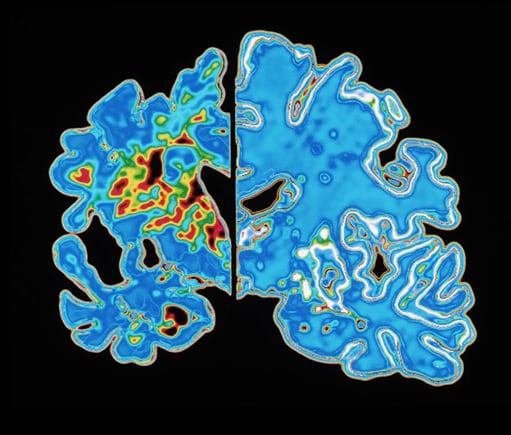

최근 미 연구팀이 혈액 속 특정 단백질의 축적 속도를 분석해 인지 장애가 나타날 시기를 역산하는 모델을 개발했다고 19일 네이처지가 보도했다. 연구 결과는 이날 국제 의학 학술지 ‘네이처 메디슨’에 실렸다. 단순히 피검사를 통해 치매 여부를 진단하는 것을 넘어, 이젠 ‘앞으로 언제 치매가 발병할지’ 타임라인까지 알 수 있다는 것이다. “알츠하이머 시계가 등장했다”는 평가까지 나온다.

알츠하이머병은 치매를 일으키는 가장 흔한 질병으로 꼽힌다. 아밀로이드와 타우 단백질이 뇌에 쌓여 발생하는 퇴행성 질환이다. 이 독성 단백질들은 증상이 겉으로 드러나기 십수 년 전부터 뇌에 쌓여 뇌 기능을 잠식한다.

미국 세인트루이스 워싱턴 대학교 의과대학 연구팀은 대규모 알츠하이머 연구에 참여한 60세 이상 성인 약 603명의 혈액 검사 결과와 인지 능력 평가 등 데이터를 분석했다. 그 결과, 혈액 속 나쁜 단백질(p-tau217) 수치가 올라가는 속도가 사람마다 놀라울 정도로 일정하다는 사실을 발견했다.

사람마다 이 단백질이 쌓이는 속도는 제각각 다를 수 있지만, 한 번 정해진 그 사람만의 축적 속도는 시간이 지나도 변하지 않고 일정하게 유지된다는 것이다. 가령 A라는 사람의 뇌에 매년 5만큼 비정상 타우 단백질이 쌓인다면, 10년 후에도 그의 뇌엔 5만큼씩 쌓이게 된다는 설명이다. 이 개인마다 다른 ‘일정한 속도’ 덕분에 발병 시점을 역산할 수 있게 됐다는 것이다.

다만, 같은 속도로 쌓여도 치매 증상이 겉으로 드러나기까지 남은 시간은 나이에 따라 달랐다. 가령 60세에 p-tau217 수치가 높게 나타난 경우엔 실제 증상이 나타나기까지 20년이 걸렸다. 반면 80세 환자의 뇌에서 비슷한 단백질 수치가 나왔을 경우엔, 11년 후 증상이 나타났다. 80세의 경우엔 노화로 인해 뇌의 기초 체력이 떨어진 상태인 만큼 증상이 더 빨리 나타난다는 뜻이다.